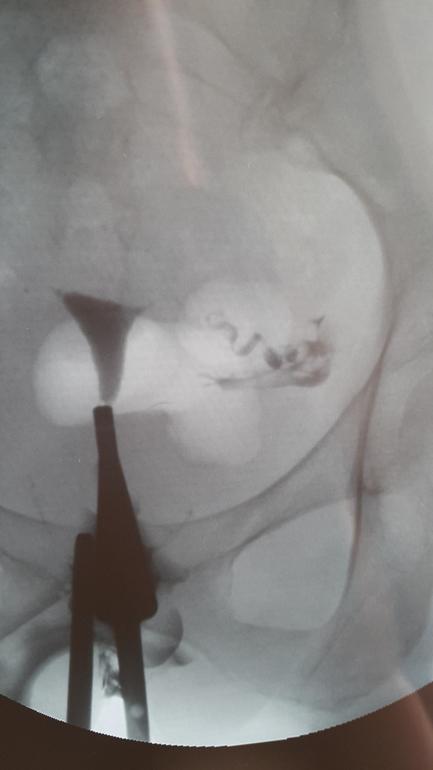

ГСГ, ЭХО, МСГ, ФертилоскопияДевочки, может кто-то разбирается, посмотрите мои снимки, пожалуйста, и скажите, сколько вам вводили контраста? У меня написано 10 мл. Это не мало? Снимки сделаны с интервалом в 30 секунд, судя по времени на них. Правой трубы нет после ВБ.

Да, в начале выхода скорее всего спайки, потому что нить жидкости оч тонкая.

Ну как не специалисту, кажется хорошо, раствор у Вас вышел (на снимке как дымок). А врач как снимок описал?

Он написал, что выход контраста ограничен перитубарными спайками. Сказал, отрицать вариант ЕБ не могу. очень немногословен был. Смутило кол-во контраста, в прошлый раз у Олейника в меня влили в 2 раза больше